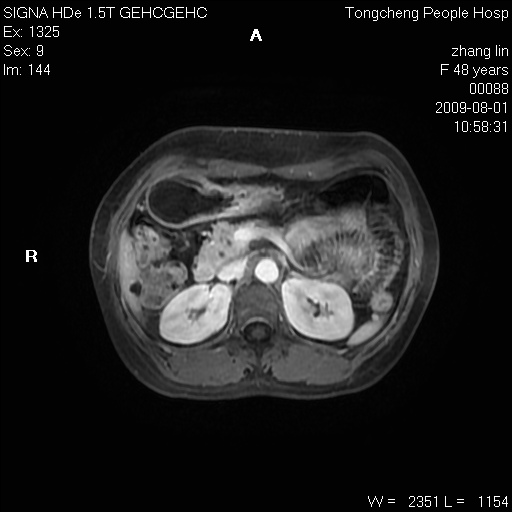

女,48岁。健康体检,彩超发现右肾占位性病变。平素健康。

临床诊断:右肾占位性病变,性质待定(囊肿?肿瘤?)。

上中腹部mr平扫+增强扫描,图像如下:

右肾上极见一类圆形病灶,t1wi呈等信号t2wi呈等高混杂信号,三期增强无强化,边界清---考虑囊肿出血。

同反相位均表现为等信号,病变无强化,考虑含蛋白的囊肿可能,弥散加权相或许有些帮助,

慢性胆囊炎